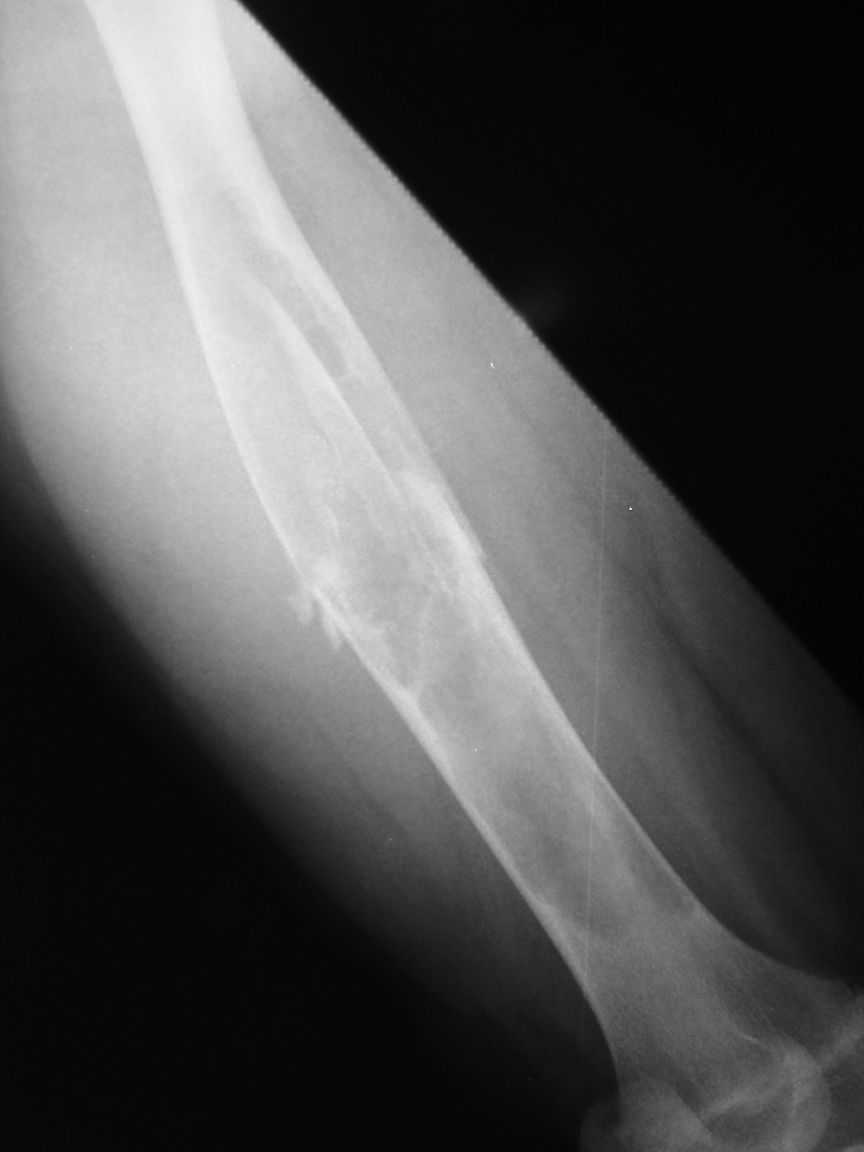

[Ortho] Pathological fracture femur

The attached xrays are of a 13 year old girl, who presented to us

with a history of trivial trauma.  X-rays showed a pathological fracture

right femur through a large radioluscent expansile lesion. All

blood investigations are normal. Clinically no other positive findings.

We assume this to be a case of fibrous dysplasia, and plan to do a

biopsy from the site. Would like your opinion regarding any other

possibility in the diagnosis and treatment options.